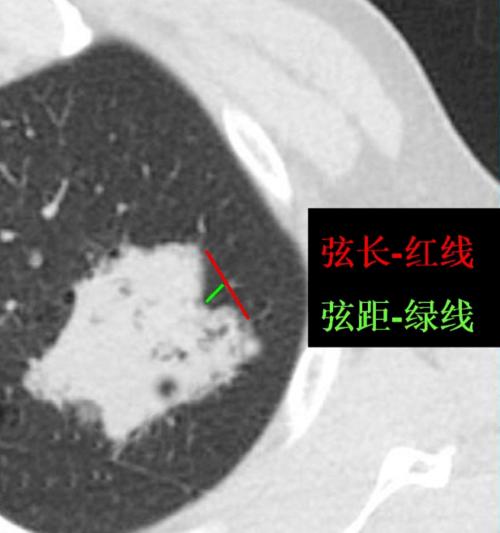

肺炎性假瘤ct表现图片

肺炎性假瘤ct表现图片,普通肺炎ct表现图片

肺炎性假瘤

= 3/10 为中分叶;肺癌常见深分叶错构瘤及结核球可呈浅分叶,炎性假瘤

图3-21a 炎性假瘤

结核球与炎性假瘤只能称之为胸膜线影或尖角征.